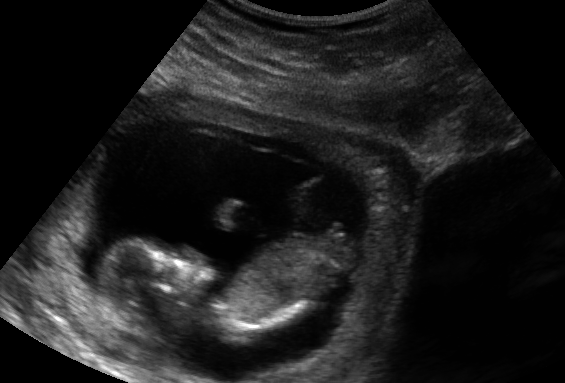

Attachment 13396Hi! Here are my ultrasound pictures from today. I would love any guesses. I am just not sure?

Going by pic 2, maybe boy?

*IF* that's the nub I'm seeing, it is angled sort of up.

Going by pic 1 I would say boy!

Boy i think...

Think maybe boy x